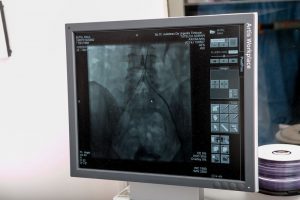

Prima intervenţie a fost făcută la o pacienta de 24 de ani, care a fost diagnosticată cu sindromul May Thurner, care a cauzat o tromboză gravă venoasă.

“Această am tratată împreună cu doctorul Tutelcă cu ceva timp, tot endovascular, trombul respectiv a fost dizolvat, dar a rămas pe loc cauza. Cauza fiind o strâmtoare a unei vene principale a corpului în interiorul abdomenului. Acest sindrom a fost tratat astăzi cu un stent special, este un tratament care este considerat standard în această boală şi avem marea bucurie să-l fi pus împreună pentru prima dată la noi.”, a spus Mihai Ionac, şeful Clinicii de Chirurgie Vasculară.

“Avantajele unei astfel de intervenţii sunt că pacientul rămâne fără simptome. SImptomele principale constau prin faptul că după ce face efort, fiind vorba de un pacient tânăr, el simte tensiune, presiune în piciorul bolnav, din cauza că sângele nu se poate drena în cantitate suficientă către inima. Şi atunci noi punem acest stent cu care îl lărgim practic calea de scurgere a sângelui venos şi eliminăm aceste simptome.”, afirmă Mihai Ionac, şeful Clinicii de Chirurgie Vasculară.